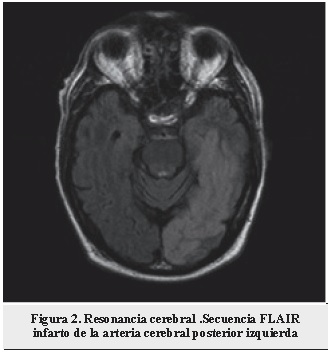

Paciente de 79 años que se encontró en el piso de su casa el día del ingreso con relajación de esfínteres y disartria marcada; la última vez que se le vio bien fue el día anterior. Se trasladó en ambulancia y se halló una hemiparesia derecha. En urgencias estaba alerta, con una afasia no fluída y hemiparesia derecha, reportaba antecedente de hipertensión arterial y diabetes tipo 2. Se llevó a una tomografía de cerebro en donde se observó un infarto del territorio de la arteria cerebral posterior izquierda, se practicó un angio-TAC en el que se descubrió una oclusión de la arteria carótida interna izquierda desde su origen luego de la bifurcación en el bulbo carotídeo (Figura 1). Se realizó una resonancia magnética que evidenció un infarto en la ubicación de la arteria cerebral posterior y de la arteria coroidea anterior en el lado izquierdo (Figura 2), con infarto talámico, del brazo posterior de la cápsula interna e infarto del uncus del hipocampo. Con una hipoplasia de las arterias cerebrales posteriores en su porción P1, con presencia de variante fetal de la arteria cerebral posterior en forma bilateral (Figura 3).

Se realizó una resonancia magnética que evidenció un infarto en la ubicación de la arteria cerebral posterior y de la arteria coroidea anterior en el lado izquierdo (Figura 2), con infarto talámico del brazo posterior de la cápsula interna e infarto del uncus del hipocampo.